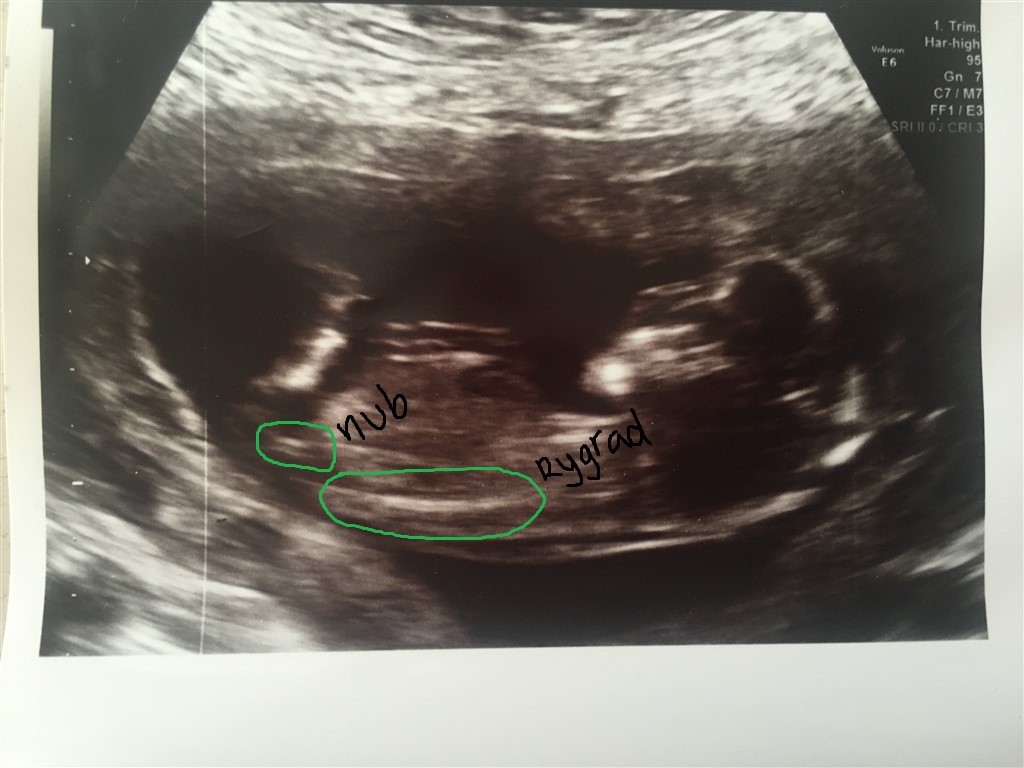

Ud fra dit scanningsbillede så siger nubben en pige da den ligger vandret

nu har jeg selv en pige og venter en dreng nu og dit billede ligner 100 % mit scannigsbillede fra min pige.. Scanningsbilledet fra min dreng er anderledes og der peger nubben mere op ad